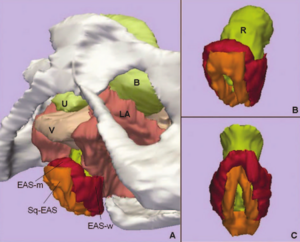

Treatment Planning and Delivery of Whole Brain Irradiation with Hippocampal Avoidance in Rats

Publication: PLoS One. 2015 Dec 4;10(12):e0143208. PMID: 26636762 | PDF Authors: Cramer CK, Yoon SW, Reinsvold M, Joo KM, Norris H, Hood RC, Adamson JD, Klein RC, Kirsch DG, Oldham M. Institution: Department of Radiation Oncology, Duke University Medical Center, Durham, NC, USA. Background/Purpose: Despite the clinical benefit of whole brain radiotherapy (WBRT), patients and physicians are concerned by the long-term impact on cognitive functioning. Many studies investigating the molecular and cellular impact of WBRT have used rodent models. However, there has not been a rodent protocol comparable to the recently reported Radiation Therapy Oncology Group (RTOG) protocol for WBRT with hippocampal avoidance (HA) which is intended to spare cognitive function. The aim of this study was to develop a hippocampal-sparing WBRT protocol in Wistar rats. Methods: The technical and clinical challenges encountered in hippocampal sparing during rat WBRT are substantial. Three key challenges were identified: hippocampal localization, treatment planning, and treatment localization. Hippocampal localization was achieved with sophisticated imaging techniques requiring deformable registration of a rat MRI atlas with a high resolution MRI followed by fusion via rigid registration to a CBCT. Treatment planning employed a Monte Carlo dose calculation in SmART-Plan and creation of 0.5 cm thick lead blocks custom-shaped to match DRR projections. Treatment localization necessitated the on-board image-guidance capability of the XRAD C225Cx micro-CT/micro-irradiator (Precision X-Ray). Treatment was accomplished with opposed lateral fields with 225 KVp X-rays at a current of 13mA filtered through 0.3 mm of copper using a 40x40 mm square collimator and the lead blocks. A single fraction of 4Gy was delivered (2Gy per lateral field) with a 41 second beam on time per field at a dose rate of 304.5 cGy/min. Dosimetric verification of hippocampal sparing was performed using radiochromic film. In vivo verification of HA was performed after delivery of a single 4Gy fraction either with or without HA using γ-H2Ax staining of tissue sections from the brain to quantify the amount of DNA damage in rats treated with HA, WBRT, or sham-irradiated (negative controls). Results: The mean dose delivered to radiochromic film beneath the hippocampal block was 0.52Gy compared to 3.93Gy without the block, indicating an 87% reduction in the dose delivered to the hippocampus. This difference was consistent with doses predicted by Monte Carlo dose calculation. The Dose Volume Histogram (DVH) generated via Monte Carlo simulation showed an underdose of the target volume (brain minus hippocampus) with 50% of the target volume receiving 100% of the prescription isodose as a result of the lateral blocking techniques sparing some midline thalamic and subcortical tissue. Staining of brain sections with anti-phospho-Histone H2A.X (reflecting double-strand DNA breaks) demonstrated that this treatment protocol limited radiation dose to the hippocampus in vivo. The mean signal intensity from γ-H2Ax staining in the cortex was not significantly different from the signal intensity in the cortex of rats treated with WBRT (5.40 v. 5.75, P = 0.32). In contrast, the signal intensity in the hippocampus of rats treated with HA was significantly lower than rats treated with WBRT (4.55 v. 6.93, P = 0.012). Conclusion: Despite the challenges of planning conformal treatments for small volumes in rodents, our dosimetric and in vivo data show that WBRT with HA is feasible in rats. This study provides a useful platform for further application and refinement of the technique. Funding:

MRI with labeled structures from atlas registered to the CBCT. Registration was carried out with the open source imaging tool 3D Slicer, Version 4.4.0. |